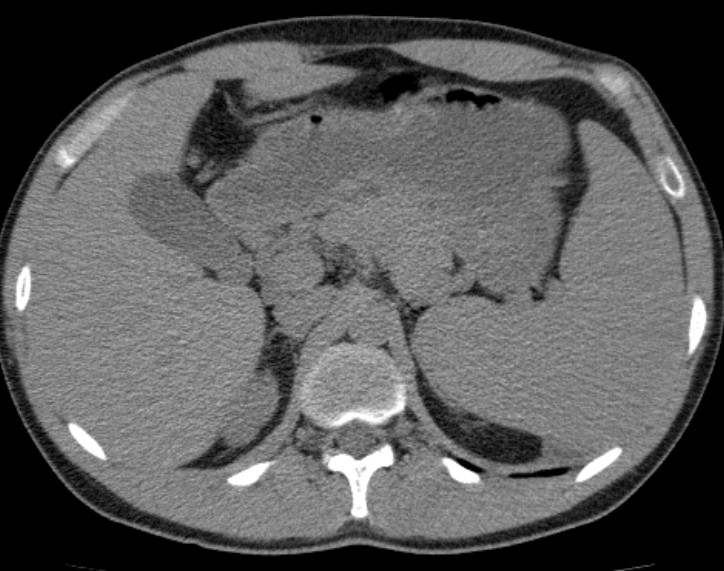

3. Рис. 2. КТ брюшной полости у пациента с ОВИН. Figure 2. Computer abdomen tomography of patient with common variable immunodeficiency | |